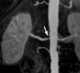

Coronary artery disease - hyperlipidemia - hypertension - diabetes - osteoporosis

Statins, also known as HMG-CoA reductase inhibitors, are a class of lipid-lowering medications that reduce illness and mortality in those who are at high risk of cardiovascular disease. They are the most common cholesterol-lowering drugs.Low-density lipoprotein (LDL) carriers of cholesterol play a key role in the development of atherosclerosis and coronary heart disease via the mechanisms described by the lipid hypothesis. [Source: Wikipedia ]